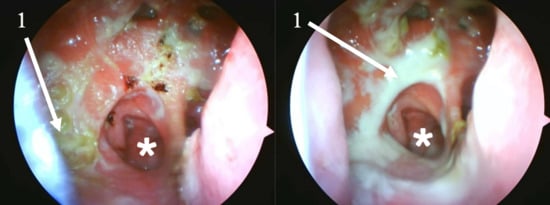

2.2. Clinical and Radiological Findings (2024)

- Mechanical Debridement: Daily endoscopic removal of all visible crusts and purulent debris was performed for the first two weeks of treatment.

| 2024 | Secondary atrophic rhinitis | Endoscopy, CT scan. Treatment initiation. 3-month follow-up. |